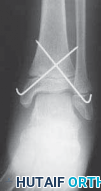

19. Many Salter type II fractures can be successfully stabilized with two 0.062-inch smooth Kirschner wires.

1. The wires are placed from distal to proximal, from the anteromedial malleolus and from the anterolateral corner of the tibial epiphysis (

TECH FIG 2

).

A B C DTECH FIG 2•

Treatment of Salter-Harris type II supination–external rotation (SER) type of fracture with interposed periosteum.

A,B.

Radiographs demonstrate a Salter-Harris type II SER type of fracture gapped anteriorly.

C.

Periosteum (shown in red) is often interposed anteriorly in SER-type Salter-Harris II fractures, which prevents closed reduction.

D.

This periosteum must be carefully extracted from the physeal fracture to obtain anatomic reduction and decrease the chance of premature physeal closure.

(continued)

TECHNIQUES E F G HTECH FIG 2•

(continued)_E,F. Open reduction was obtained after failed closed reduction due to interposed periosteum in the physeal fracture. Then the fracture was stabilized with two crossed Kirschner wires placed percutaneously. G,H. At 1 year postoperatively the distal tibial physis appears open. The _red arrows

mark the Harris growth line, which is parallel with the physis, demonstrating symmetric growth after injury. This further supports that the tibial physis is open.